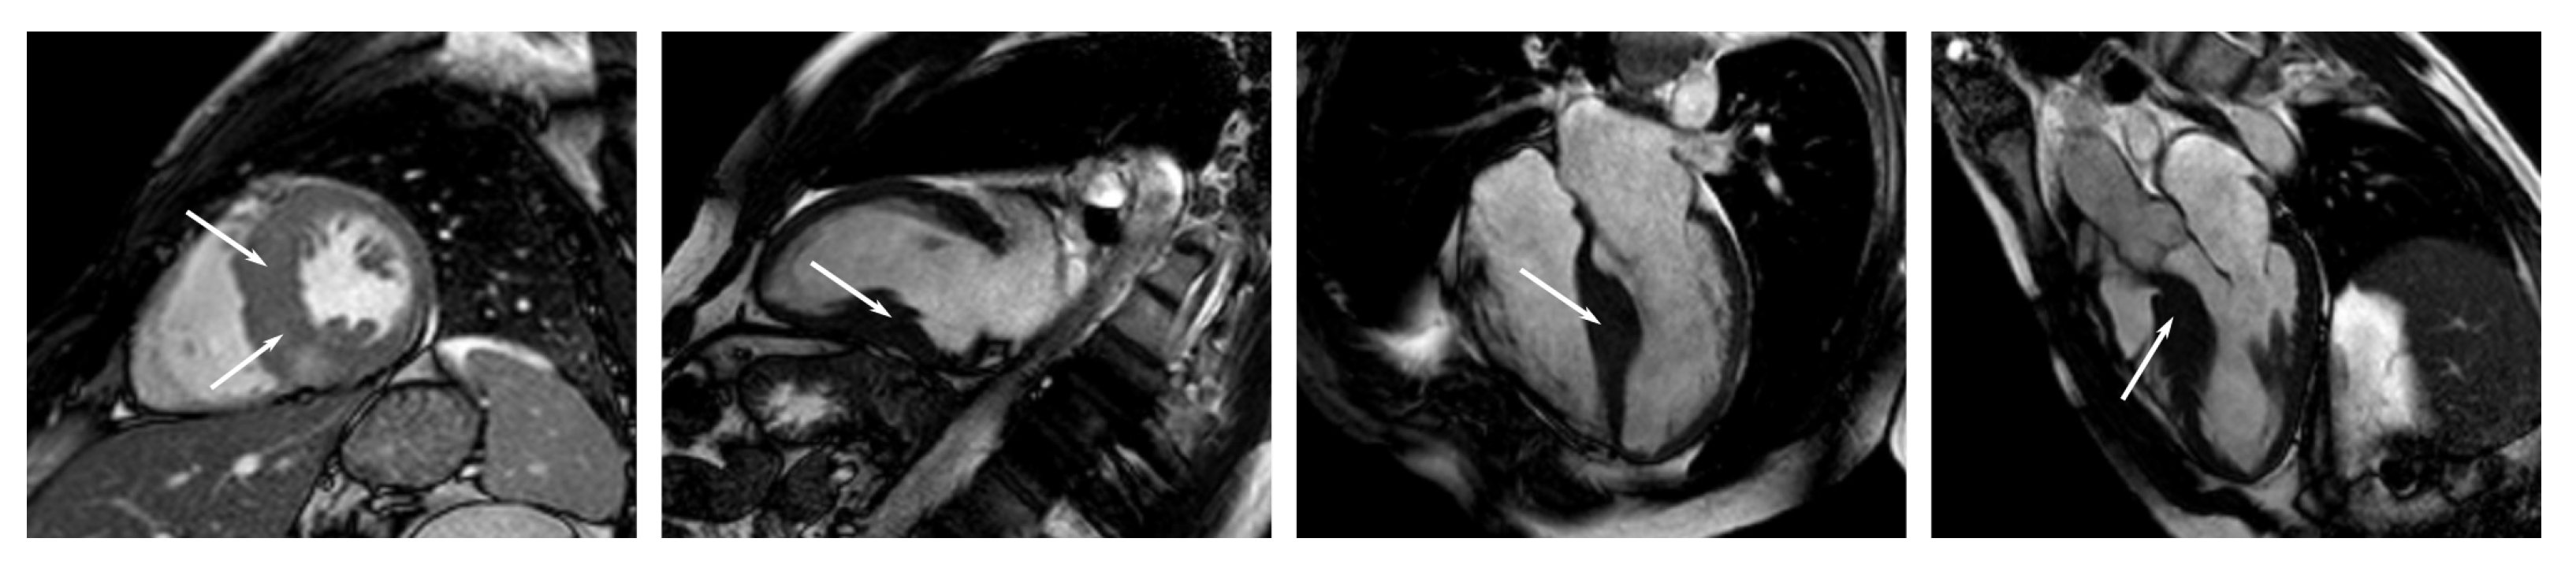

Appendix C. Example Images

- Short-axis images from the apex to the base at different stages of the cardiac cycle;

- Long-axis, two-chamber images at different stages of the cardiac cycle (heart beat);

- Long-axis, three-chamber images at different stages of the cardiac cycle;

- Long-axis, four-chamber images at different stages of the cardiac cycle.